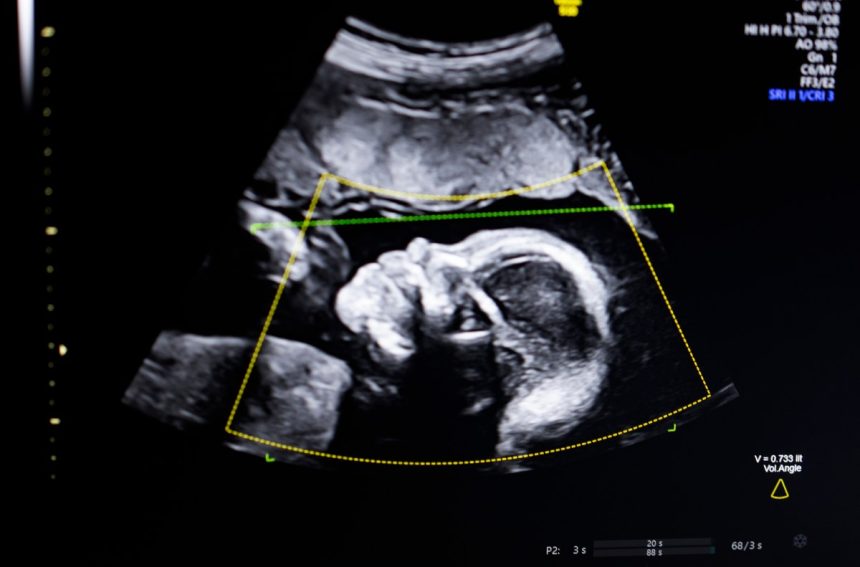

After claiming victory at the JS Disrupt Battlefield 2023, BioticsAI made a groundbreaking announcement on Monday regarding FDA clearance for their innovative AI software designed to detect fetal abnormalities in ultrasound images.

The AI technology developed by BioticsAI utilizes computer vision to enhance fetal ultrasound quality assessment, anatomical completeness, automated reporting, and seamless integration into clinical workflows. Bustami envisions that this technology will play a crucial role in addressing the concerning prenatal outcomes in the U.S., particularly among Black women who face a disproportionately high rate of maternal deaths.

Recognizing the pivotal role of prenatal ultrasound in monitoring pregnancies, Bustami emphasized the significance of addressing the challenges associated with low-quality images that can lead to misdiagnosis. Training their AI models on a diverse set of hundreds of thousands of ultrasounds, the team at BioticsAI focused on ensuring the reliability of their technology in real-world scenarios, especially among demographics with elevated risks.